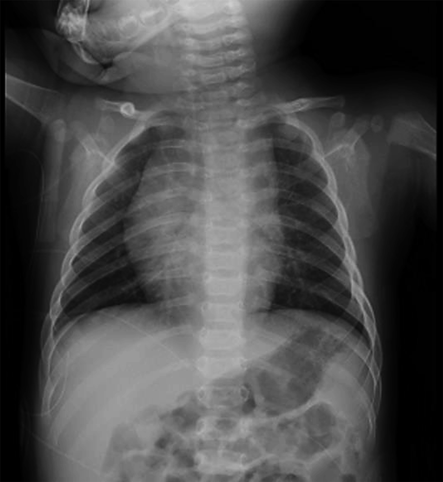

Examination findings on arrival: A simple chest X-ray showed a cardiothoracic ratio (CTR) of 50%, with no evidence of pneumonia or congestion (Fig. 2). Blood tests revealed no particular abnormalities in electrolytes or thyroid function (Table 1).